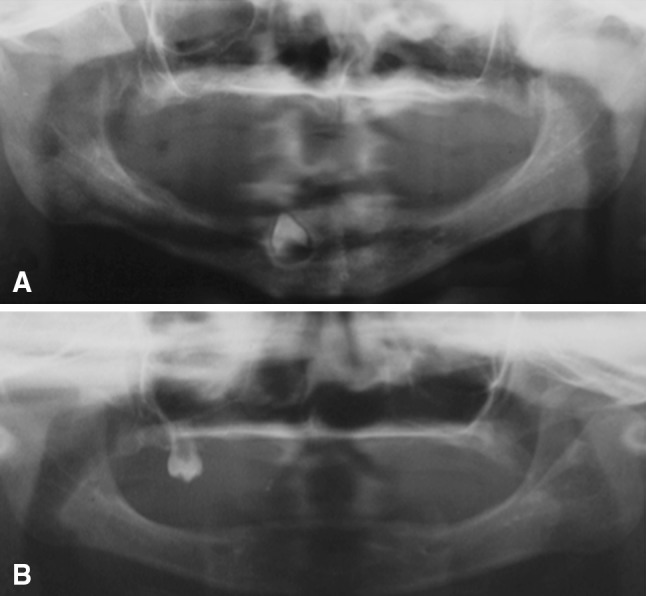

Clinical examination of the males revealed the typical features of HED. The proband (family member VII-4) presented with hypohidrosis, hypotrichosis, and missing teeth. The scalp hair, eyelashes, and eyebrows were sparse and thin. The boy was also heat intolerant. He had a characteristic facial appearance, including a prominent forehead, saddle-back nose, protruding lips, and convex nails (Fig. 2). Clinical examination of the parents revealed agenesis of the lateral maxillary incisors and conical teeth in the mother (family member VI-15). No other features of DEH were observed in his parents. A second child was a 4-year-old male (family member VII-5), who was clinically similar to the first case (Fig. 3). The boy had a characteristic facial appearance, including a prominent forehead, saddle-back nose, and protruding lips. His mother had agenesis of the lateral maxillary incisors, mandibular incisors, and mandibular molar (family member VI-16). Panoramic radiograph of the proband showed the presence of a single tooth forming in the mandibular canine region (Fig. 4a). In the second boy, oral examination and panoramic radiography showed the presence of one tooth in the maxilla (Fig. 4b).

Fig. 4.

Panoramic radiographic of two cases of X-linked hypohidrotic ectodermal dysplasia. Panoramic radiograph of the proband (VII-4) (a) and of the second boy (VII-5) (b). The congenital absence of the majority of teeth is apparent. In the first case, only one tooth is developing in the mandibular canine region. In the second, only one molar is present in the maxilla